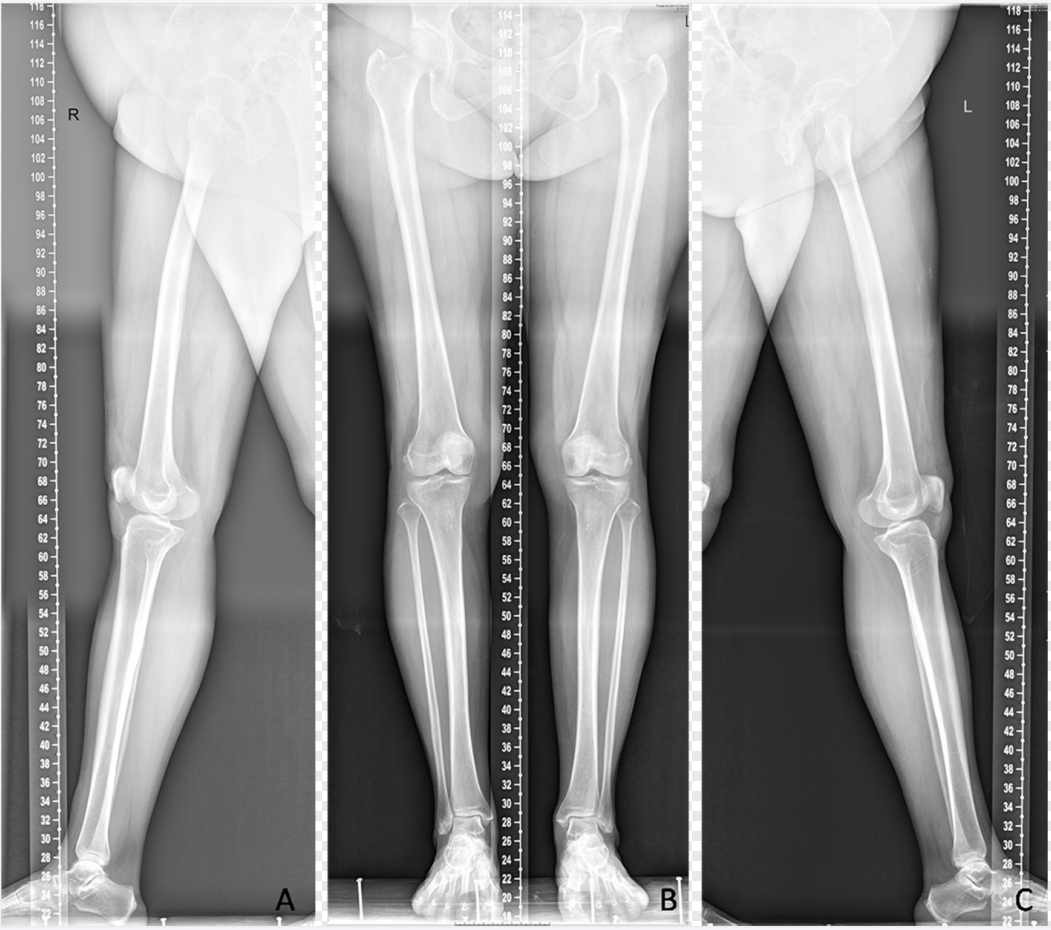

是在自动控制程序模式下,一次性采集不同位置的多幅图像,然后由计算机采用精确配准技术进行无缝全景拼接,合成为大幅面X线图像。临床上主要应用于骨关节系统疾病,如脊柱侧弯矫形、下肢矫形及人工关节置换等,可显示病变范围和全脊柱或肢体的整体受力状态,常见体位包括脊柱与双下肢全长摄影(图5、图6)

dr数字怎么用数字化X线摄影术(DR)_https://www.jmylbn.com_新闻资讯_第8张

图6  双下肢全长拼接